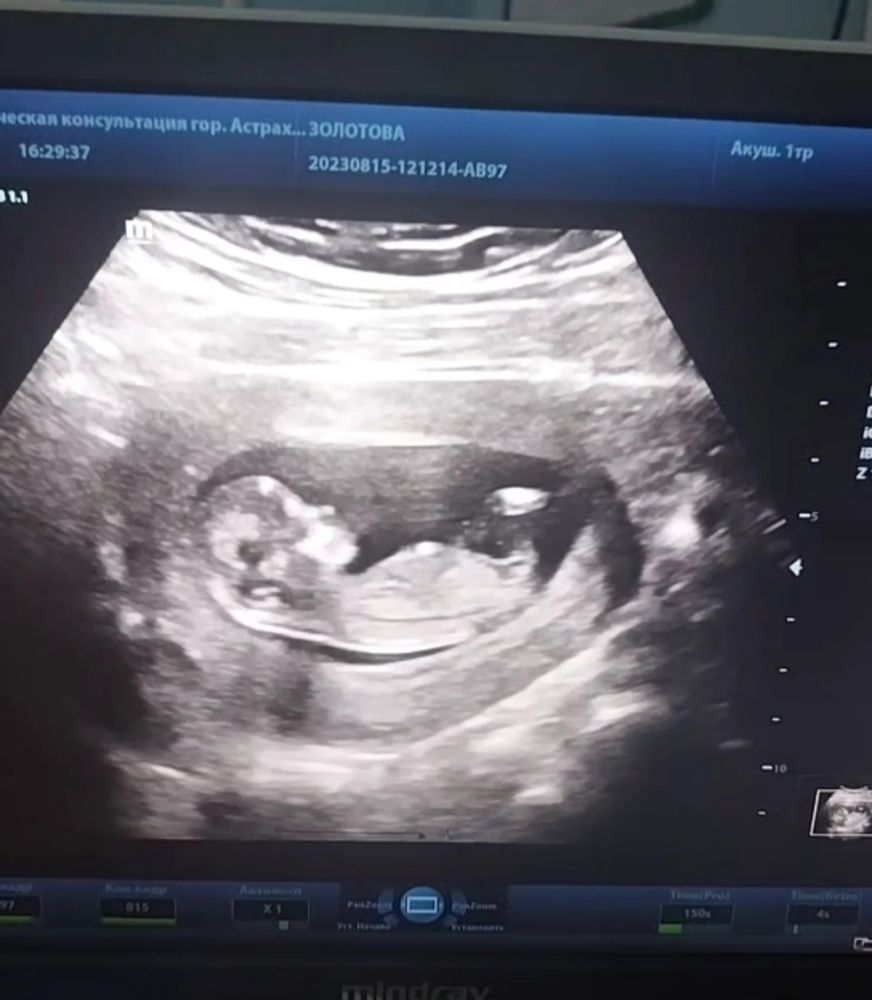

Викки в Благополучная беременность 2 года На память 🥰😘💕🤰 12+5, 15.08.2023 первый скрининг ❤️6,1см, сб 158 !😍😍😍 Посмотрите еще 20 записей на эту тему Лучший ответ Lelya Хорошенький 💕 05.09.2023 Ответить Викки Lelya, как у вас дела? 05.09.2023 Ответить Lelya Викки , все хорошо, тоже растём. Скрининг 2 недели назад прошла. Теперь жду приём врача и должны назначить цервикометрию и второй скрининг 06.09.2023 Ответить Отменить Ответить Александра 🥰💞 06.09.2023 Ответить Лиса Какая красота😍😍😍 05.09.2023 Ответить Викки Лиса, ты как, дома?? 05.09.2023 Ответить Лиса Викки , да, дома. Хорошо что сейчас в отпуске 05.09.2023 Ответить Ясенька Какой милый профиль❤️🥰есть предположения кто в домике ? 05.09.2023 Ответить Викки Ясенька, есть)) но я не хочу смотреть до определённого срока 05.09.2023 Ответить Ясенька Викки , 🥰 05.09.2023 Ответить 3 раз как в 1 раз 😁 Анализ мочи, вопрос Чаты Беременных Выберите чат: Январята-2026 Февралята-2026 Мартята-2026 Апрелята-2026 Майчата-2026 Июнята-2026 Июлята-2026 Августята-2026